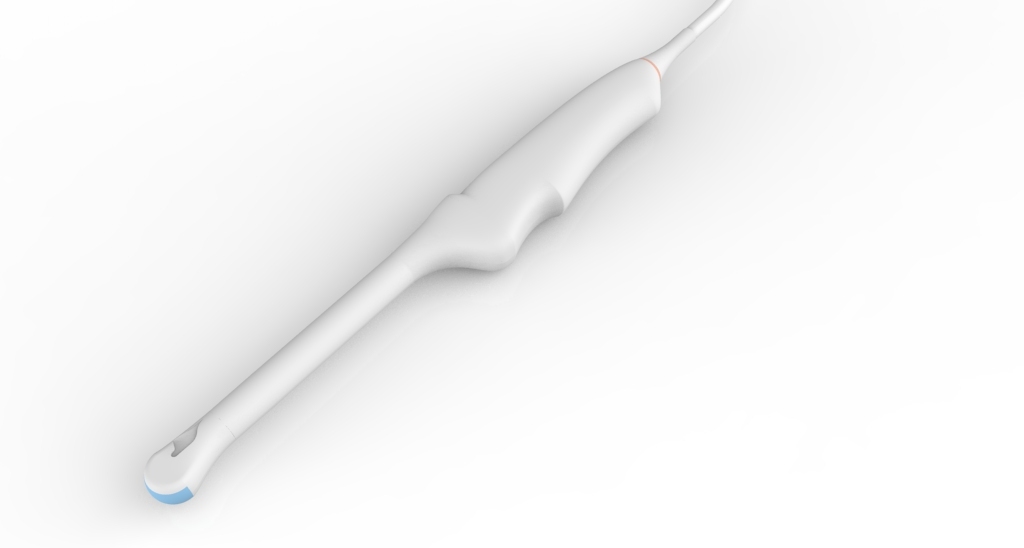

Внутриполостной E8-4QL17-7Q

Внутриполостной E8-4Q

Трансвагинальный E8-4D

Трансвагинальный E612UB